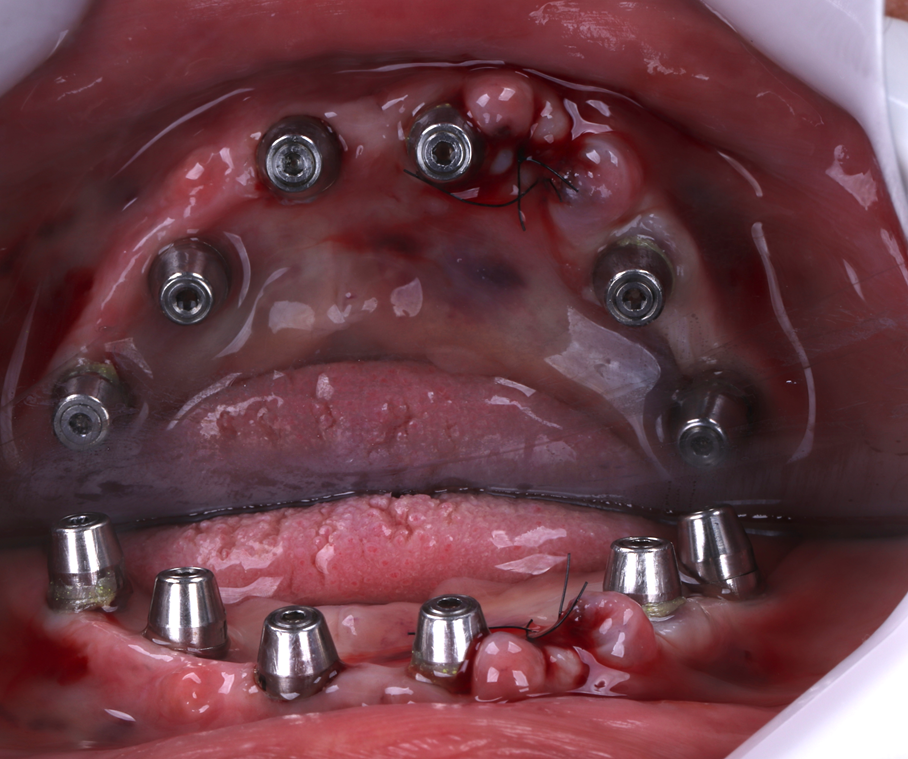

A cirurgia teve início com a exodontia do elemento 33, seguida da realização de anestesia infiltrativa em fundo de saco para a fixação do guia cirúrgico. Com o guia devidamente posicionado e estabilizado, foram administradas anestesias adicionais por meio das anilhas direcionadas a cada sítio implantado. Em seguida, foi realizada a sequência de fresagem e instalação dos seis implantes conforme o planejamento prévio. O procedimento cirúrgico teve duração aproximada de 30 minutos, sendo necessária apenas uma sutura na região da exodontia.

Figura 15 – Raio-X panorâmico pós-operatório com os seis implantes posicionados e os mini-cônicos instalados.

Figura 16 – Foto do pós-operatório imediato.

Figura 17 – Foto do pós-operatório imediato.

Logo após a instalação dos implantes foram posicionados mini-pilares cônicos em cada implante. Após 28 dias, os mini-pilares cônicos foram torqueados com 30N, e realizou-se a moldagem para confecção da prótese definitiva, em resina, respeitando o protocolo de carga precoce.